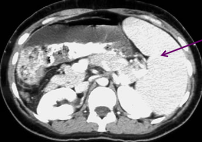

Trv Pancreas Head- anterior to IVC with CBD

(more sag hold from hamburger to right little)

Trv Pancreas Neck- uncinate process and SMV (hamburger)

Trv Pancreas Body- SV, CA/SMA level

Trv Pancreas Tail- SV and left kidney